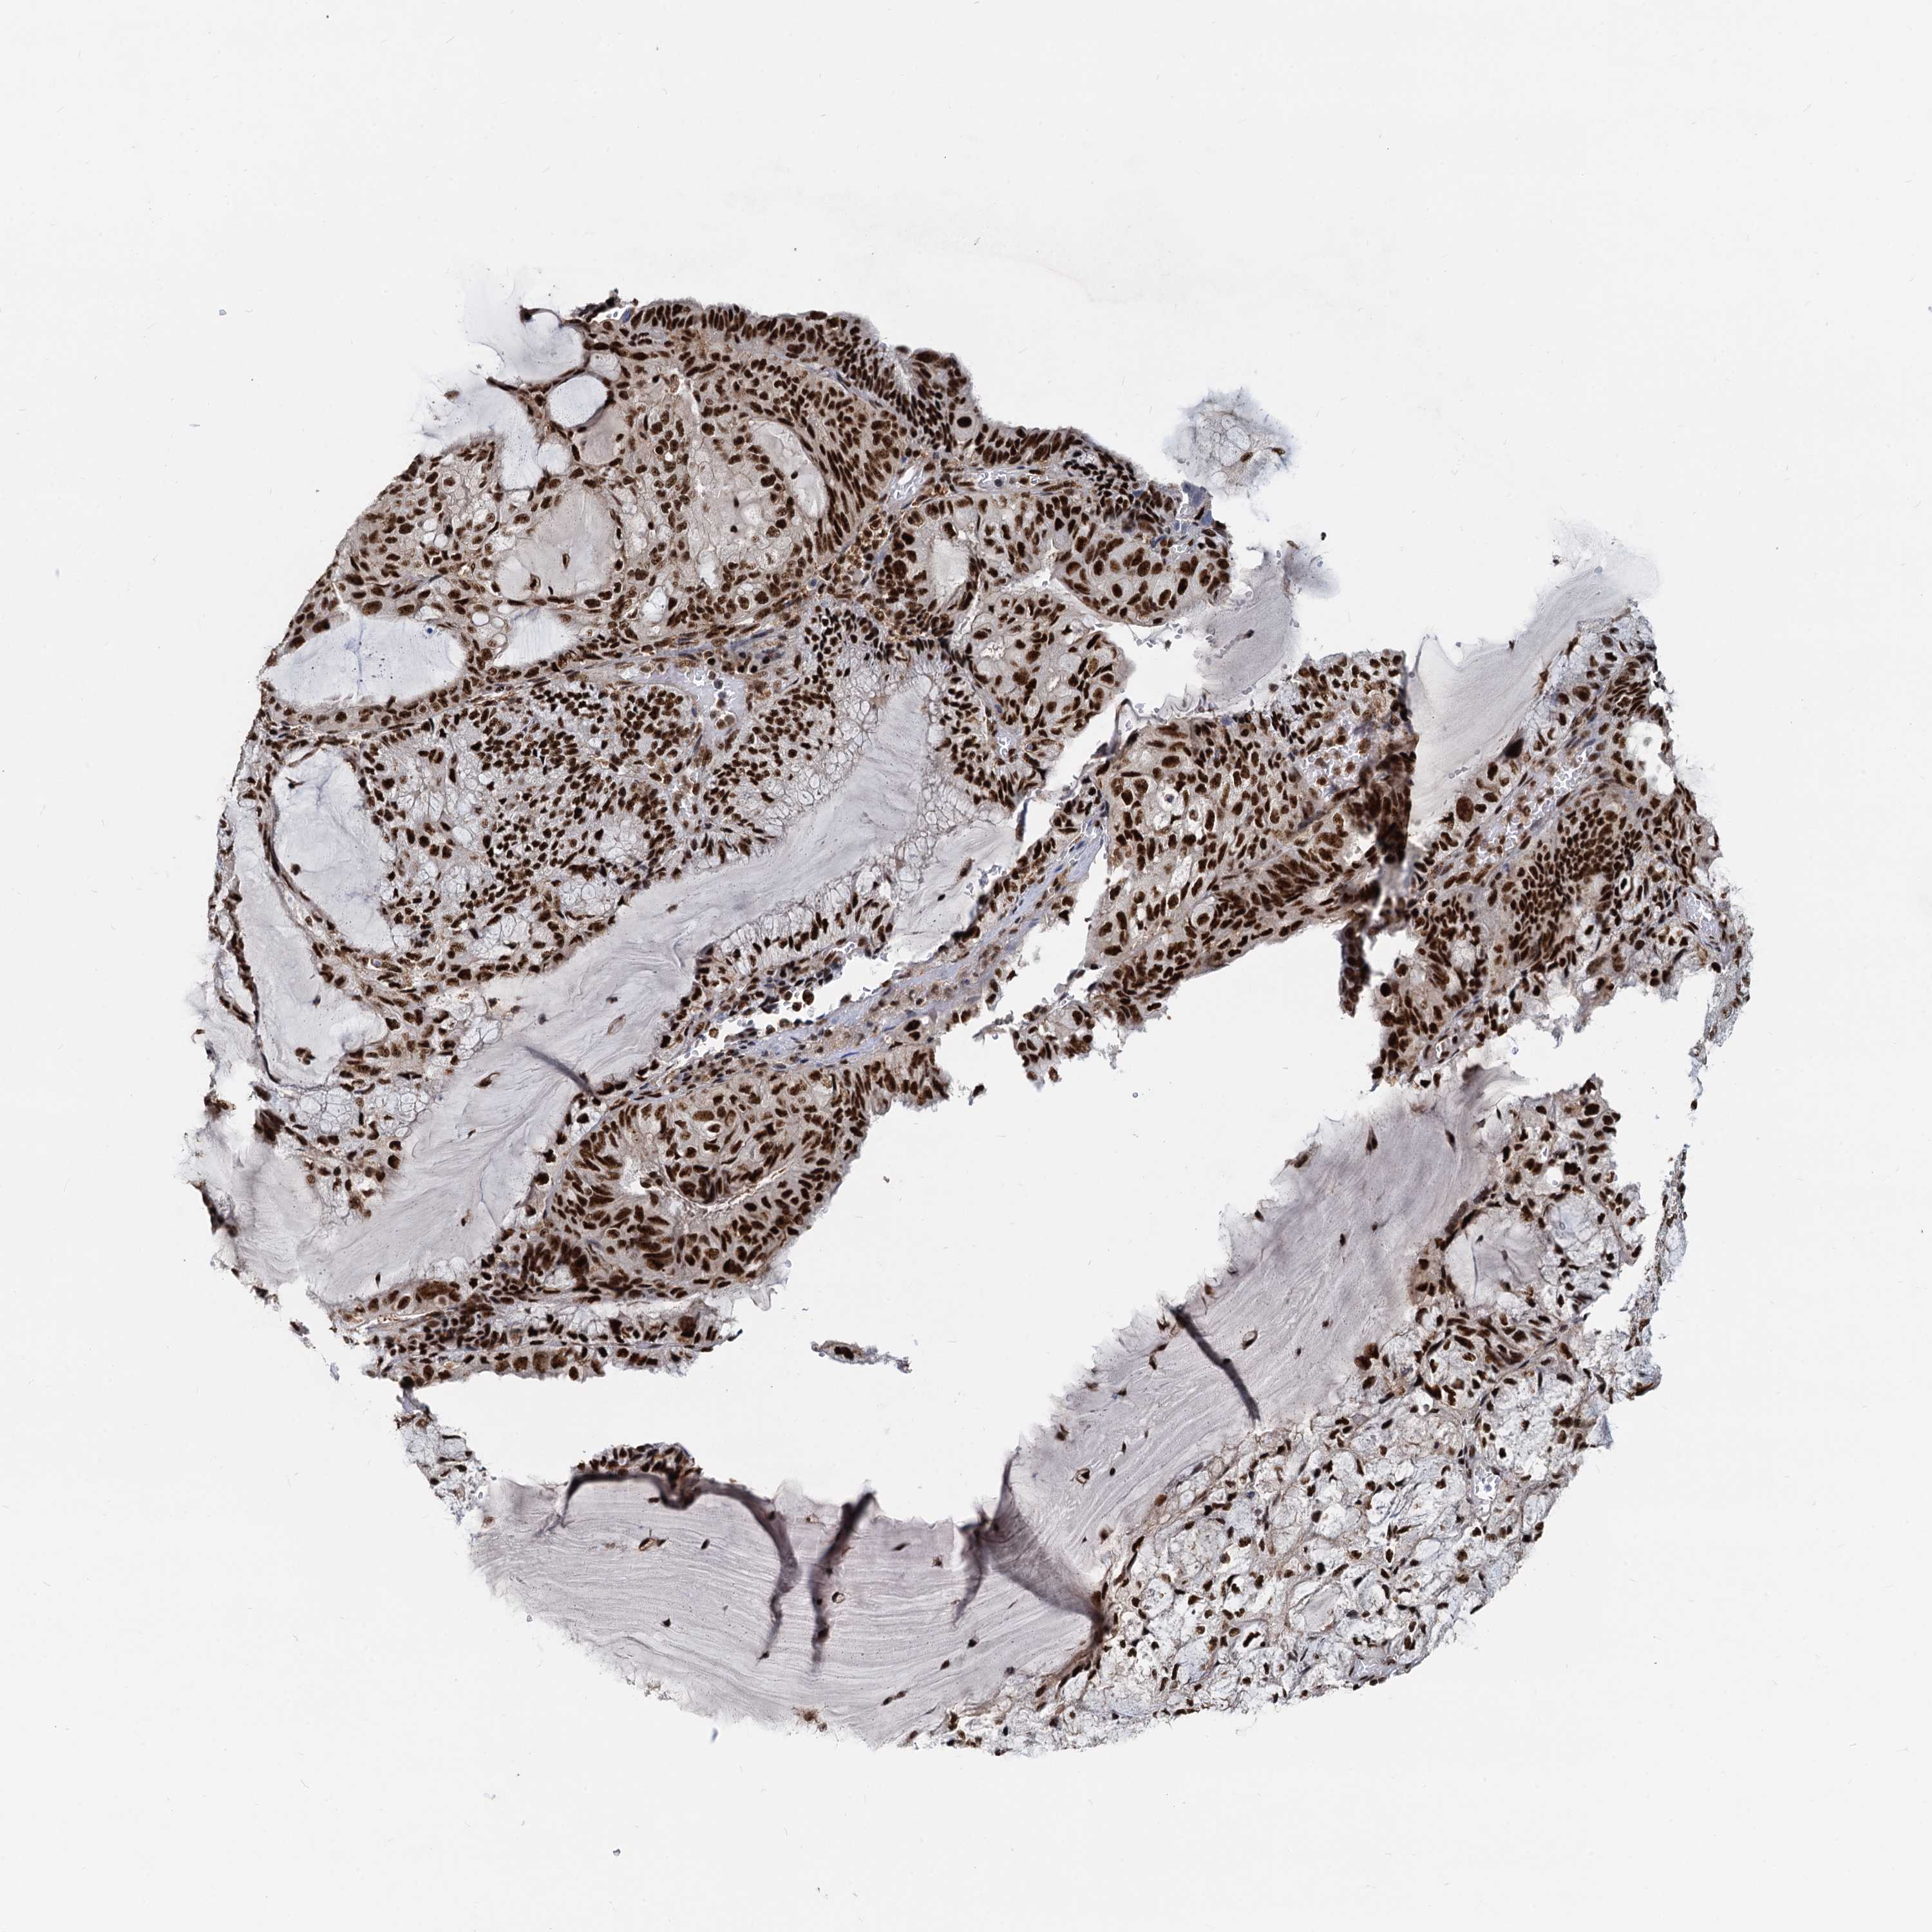

ENDOMETRIAL CANCER - Protein expressioni

A mouse-over function shows sample information and annotation data. Click on an image to view it in a full screen mode. Samples can be filtered based on level of antibody staining by selecting one or several of the following categories: high, medium, low and not detected. The assay and annotation is described here.

Note that samples used for immunohistochemistry by the Human Protein Atlas do not correspond to samples in the TCGA dataset.

Antibody stainingi

Antibody staining in the annotated cell types in the current human tissue is reported as not detected, low, medium, or high, based on conventional immunohistochemistry profiling in selected tissues. This score is based on the combination of the staining intensity and fraction of stained cells.

Each image is clickable and will lead to virtual microscopy that enables deeper exploration of all samples and also displays staining intensity scores, fraction scores and subcellular localization as well as patient and tissue information for each sample.

Antibody HPA040252

Staining

High

Medium

Low

Not detected

Intensity

Strong

Moderate

Weak

Negative

Quantity

>75%

75%-25%

<25%

None

Location

Nuclear

Cytoplasmic/membranous

Cytoplasmic/membranous,nuclear

Adenocarcinoma, NOS

Adenocarcinoma, metastatic, NOS